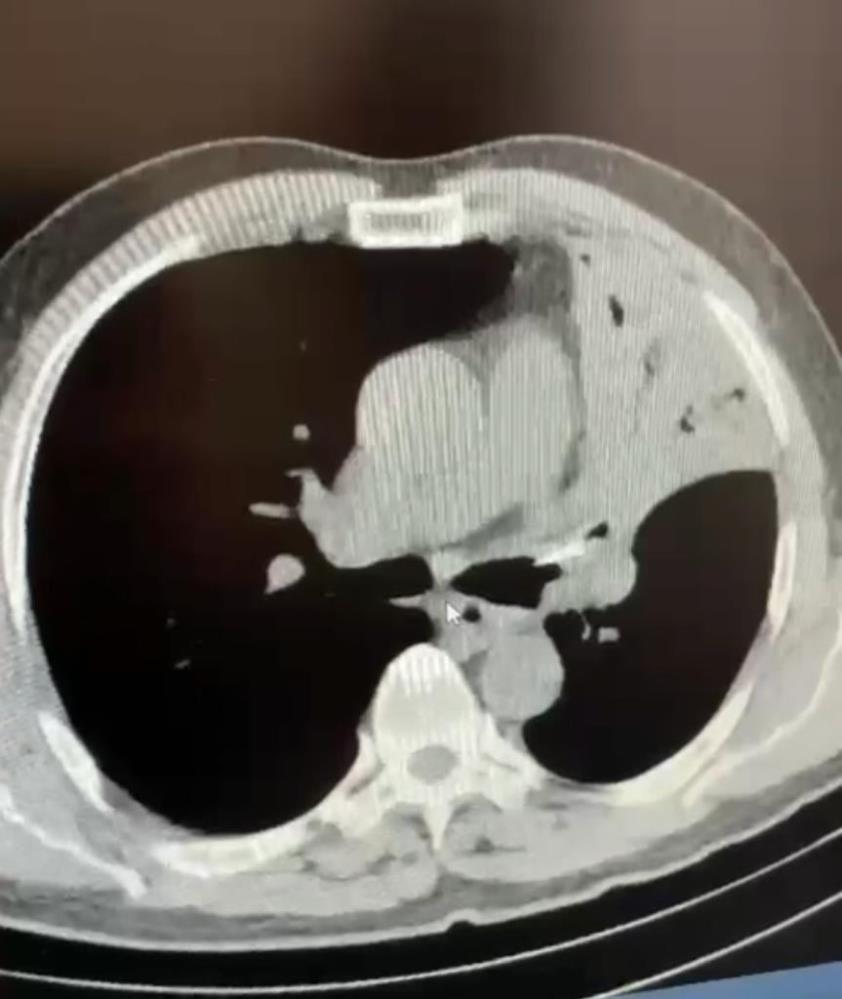

Bolu’da şaşkına çeviren bir olay yaşandı, öksürük ve şiddetli ağrı şikayetiyle gittiği hastanede 5 yıldır sol akciğerine saplanan lades kemiğiyle yaşadığını öğrenen Mehmet Salih Fer, kemiğin ameliyatla alınması sonucu sağlığına kavuştu.

Düzce’nin Cumayeri ilçesinde yaşayan Mehmet Salih Fer, uzun süredir devam eden öksürük ve şiddetli ağrı şikayetiyle AİBÜ İzzet Baysal Eğitim ve Araştırma Hastanesi’ne gitti. Fer’in yapılan muayenesinde sol akciğerine lades kemiği saplandığı tespit edildi. Fer’in 5 yıl boyunca akciğerinde saplanmış halde bulunan lades kemiği yapılan ameliyatla alındı. Sağlığına kavuşan Fer, yapılan son kontrollerinin ardından taburcu edildi.

5 yıl boyunca öksürük, şiddetli ağrı sırtında yanma şikayetleri bulunduğunu ifade eden Mehmet Salih Fer, “Aynı şikayetlerle hastanelere gittim, muayenelerim yapıldı, filmler çekildi. Sık sık enfeksiyon geçiriyordum, farklı farklı tanılar konuldu ve ilaç tedavileri başlatıldı. Ancak hiçbir sonuç alamadım ve şikayetlerim devam etti. Son olarak İzzet Baysal Eğitim ve Araştırma Hastanesi Göğüs Cerrahisi kliniğine geldim. Burada doktorlarım tarafından muayenelerim ve tetkik işlemlerim yapıldı. Neticede sol akciğerimde yaklaşık 5 senedir bir lades kemiği ile yaşadığımı öğrendim” dedi.